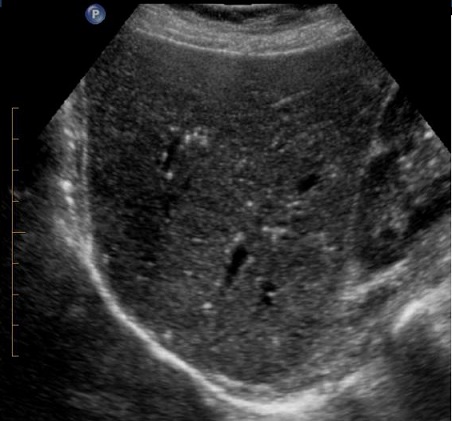

Image echographique de steatose du

foie est image du foie de plus en plus hyperechogene

homogene . Si la steatose est

important les branches de la veine porte sont

moins de visible et les structures profonde du foie

deviennent difficile a visualise . --Diagnostic echographique

de steatose du foie se represence lorsque le paenchyme

hepatique est beaucoup plus hyperechogene que le rein droit

. Au stade agrave , hepatomegalie et dilatation de veine

splenique et splenomegalie peut se en voyaient . Image de

distortion vasculaire sur Doppler en couleur et

amortissement du flux sanguine de la veine porte . Technique

echoelastographie peut en differencier que le foie steatose

est plus dure que foie normale .

Image echographique d'une

steatose du foie . la parenchyme du foie est tres

hyperechogene Les vaisseaux du foie sont en

moindre visible |

Steatose du foie : La

parenchyme du foie est plus riche de echogene que le

rein . Et le bord du diaphragme en arriere est

en moins de visible . |